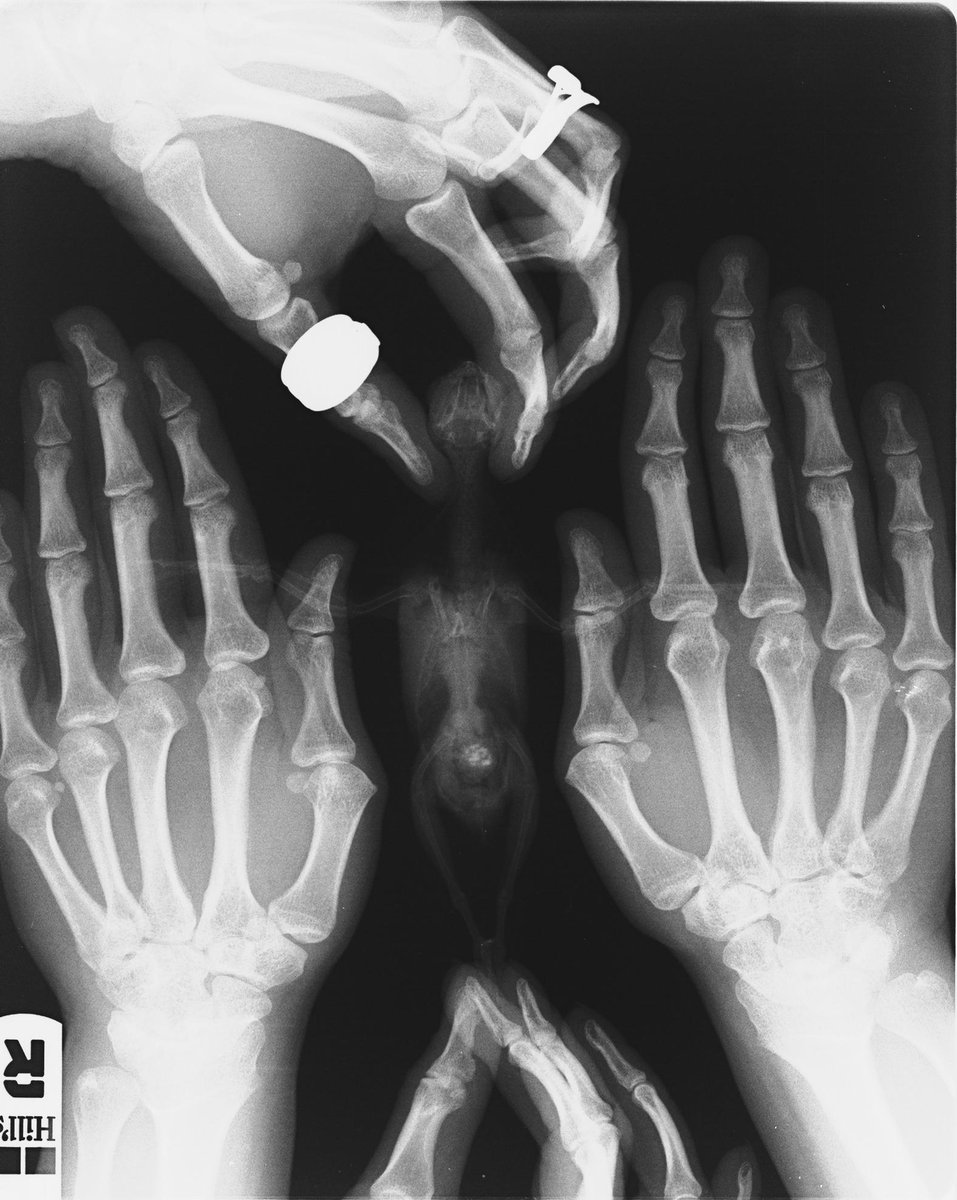

Добрый день! Побывали вчера у орнитолога Лешковой М.А, замечательный доктор. К сожалению, рентген показал онкологию семенников, достаточно крупную. Все будет зависеть от того, насколько быстро она будет расти, врач сказала что живут птички с таким и по 6 лет. Через 4 месяца поедем на повторный рентген - будем мониторить динамику роста опухоли. Анализ подтвердил мегабактериоз. Назначенное лечение: Нистатин 500.000 1/2 таб. на 1 мл. воды по 0,1 мл. 2 раза в день - 45 дней. Дифлюкан порошок, развести по инструкции, давать по 0,06 мл. 2 раза в день - 30 дней. Локсиком суспензия 0,5 мг/мл. - по 0,09 мл. 2 раза в день, поить постоянно на протяжении жизни. Докармливать кашей Hainz безмолочной - 38 градусов. Строгая диета, исключить обычный корм и мин. песок, кормить запаренным овсом. В июле на повторный анализ и осмотр.

Фото рентгена и анализа прилагаю, как обещала: